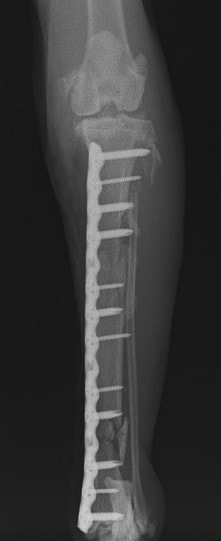

脛骨骨折 : 症例1 | 症例2 | 症例3 | 症例4 | 症例5

Advanced Locking plate system と Locking compression plate system

当院ではAdvanced Locking plate system(ALPS)と、Locking compression plate system(LCPS)という骨接合法で骨折症例の治療を行っています。

Locking Compression Plate

LCPは、スクリュー(ネジ)とプレート(金属の板)をロックする特殊な構造により骨折部位を固定する新しい世代のプレートシステムです。ひとつのホールでロッキングスクリューとスタンダードスクリューの使用を選択できるユニークな構造をしているため、骨折断端間の圧迫を目的とした従来型プレート固定法に加え、高い角度安定性を有するロッキングスクリューを用いた固定法の選択が可能です。従来のプレートシステムでは困難だった部分の骨折や癒合不全の症例に高い治療効果をもたらします。